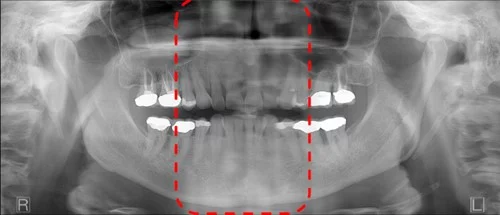

Chin too high or too low

These are also probably a little more obvious for the operator. The first shows the chin positioned too high and therefore, the occlusal plane is at too high of an angle.

Conversely, this patient has the chin too low such that the occlusal is pointing down.

Addressing both of these issues comes down to making sure the occlusal plane is just slightly tipped (~10 degrees) downward. In our experience, we often find that the chin too far up is a more common error. One of the root causes of this is that sometimes the patient is simply nervous. A nervous patient may have a defensive posture that is trying to keep the rest of the body “out of the machine” – which can present as the chin jutting out and up.

To address this issue, there is the obvious technique of raising or lowering the chinrest on your panoramic x-ray and use the laser alignment system to double check this occlusal plane angle. However, another tip is to perform this check last before walking out of the room to initiate the scan.